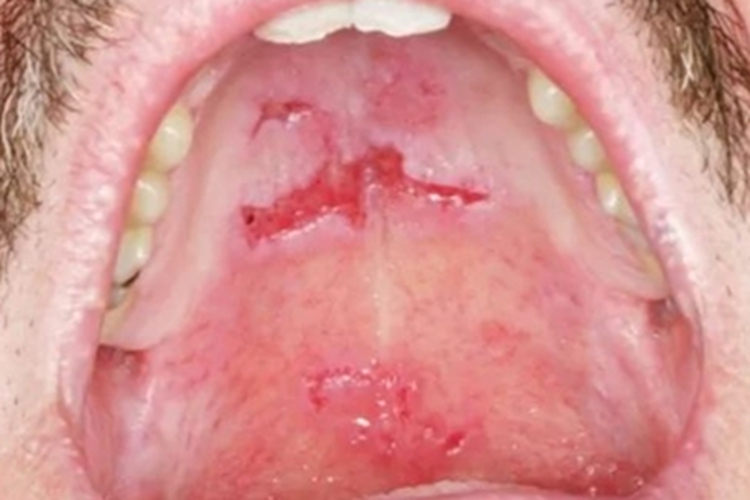

副肿瘤性天疱疮可累及口腔,出现局部糜烂,形状不规则,大小不等,糜烂面呈红色或粉红色,与周围黏膜边界较清晰,患者自觉有疼痛感。